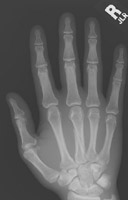

- Click on the image for a larger versionAPA radiograph of the hand. This demonstrates a comminuted fracture of the base of the fifth metacarpal.